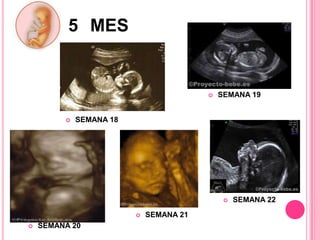

El documento describe las etapas del embarazo, incluyendo sus síntomas iniciales. Explica que el embarazo se divide en tres trimestres, el primero de las semanas 1 a 12, el segundo de las semanas 13 a 27, y el tercero de las semanas 28 a 40, cuando ocurre el parto. Detalla los cambios fisiológicos que ocurren en cada semana del embarazo.